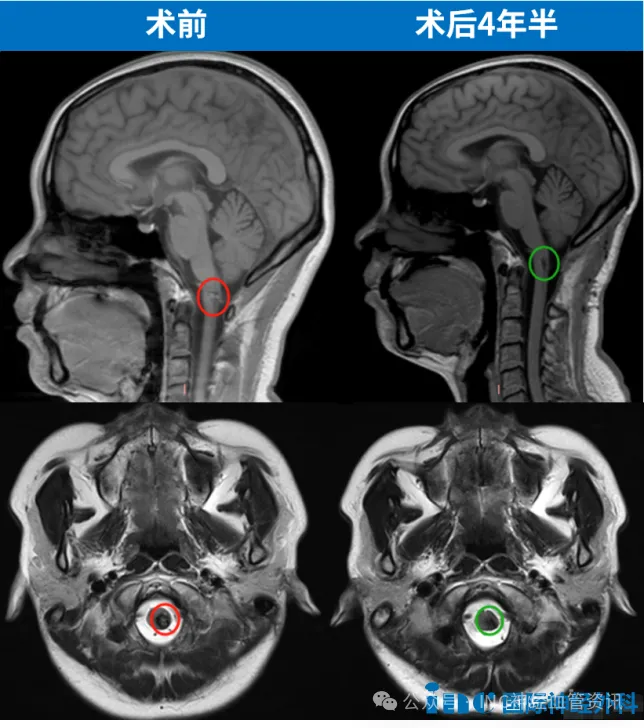

手术实施过程顺利,患者仅需ICU观察一天即转回普通病房。术后第五天可下床活动,第十二天出院。术后MRI证实病变完全切除,困扰四年的脑血管疾病得到根治。

王女士历经四年决策过程,最终成功通过脑干手术重获健康。该案例表明:面对复杂疾病,需要充分了解病情、科学评估风险并适时采取行动。